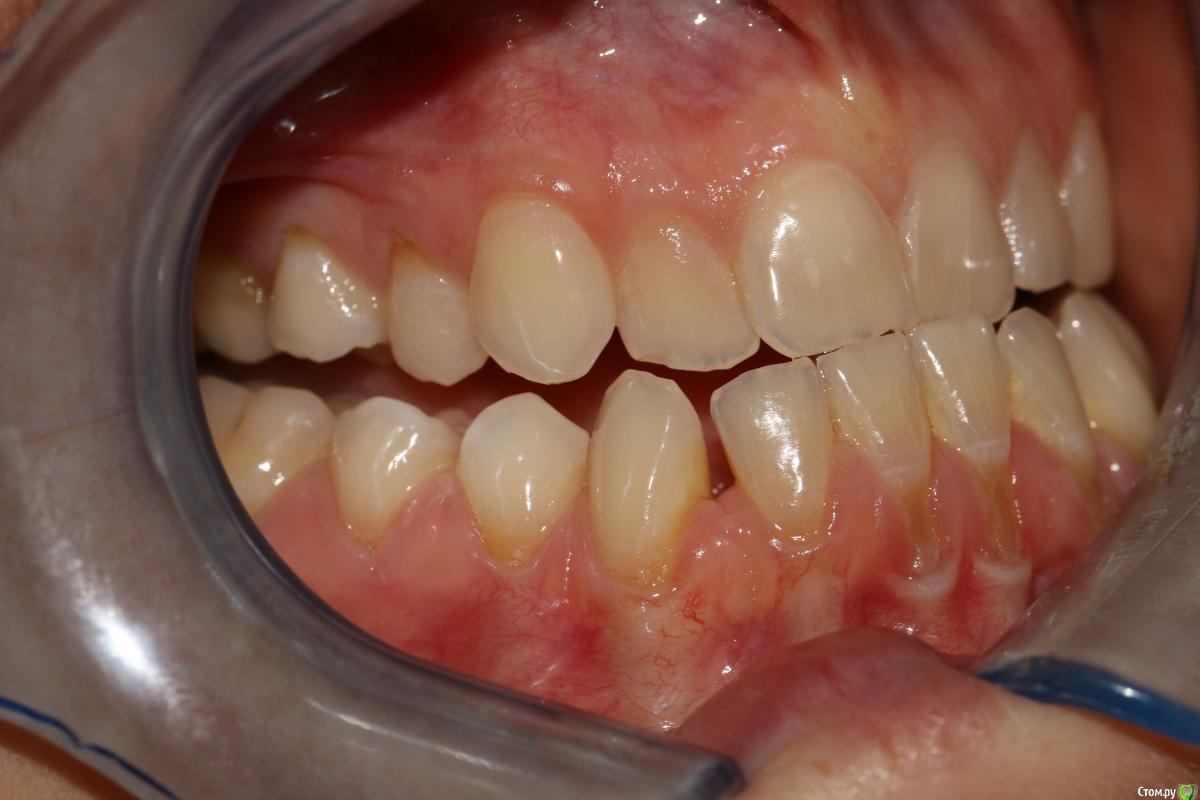

rytovst Опубликовано 15 сентября, 2018 Поделиться Опубликовано 15 сентября, 2018 Здравствуйте ,коллеги!Посоветуйте ,как и чем лучше закрыть данные рецессии перед ортодонтическим лечением.Склоняюсь к расщепленному лоскуту и ССТ с неба + коронально-смещенный лоскут . Может быть взять ССТ с эпителиальной полоской? Ссылка на комментарий

rytovst Опубликовано 16 сентября, 2018 Автор Поделиться Опубликовано 16 сентября, 2018 -фото ,как вы видите ,не в прикусе ( 6 зубы не смыкаются) -дистальная дизокклюзия - произвести протрузию на нч Ссылка на комментарий

Irouil Опубликовано 16 сентября, 2018 Поделиться Опубликовано 16 сентября, 2018 зачем тогда спрашивать, если сделаете, как нравится?Скейлинг + ЭДТАМожет коллега с Вас пример берет: уже все сделал, а спрашивает из спортивного интереса?) Я бы тоже в резцах шел с эпителием и туннель, в клыках/премолярах может полностью деэпителизировать (если не одним трансплантатом брать будете). В этом случае, имхо, показания к пародонтологии даже без ортодонтии Ссылка на комментарий

Дмитрий Л. Опубликовано 16 сентября, 2018 Поделиться Опубликовано 16 сентября, 2018 В этом случае, имхо, показания к пародонтологии даже без ортодонтии Я не об этом. Если резцы планируется сдвинуть дистально, то рецессия может уменьшится уже уже от этого, соответственно и успех хирургии будет выше после ортодонтии, а не до. - произвести протрузию на нч Вот честно я не понял здесь вас( Вообще здесь не рецессия, а пародонтит. И устранить нужно причину. Уздечка, преддверие...?+1 за туннель и не уверен по поводу коронарного смещения лоскута: риск порвать лоскут + натяжение от губы только увеличится. Ссылка на комментарий